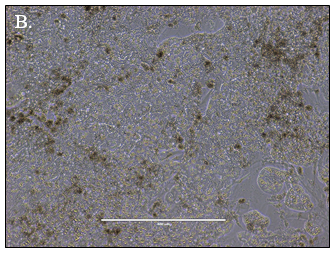

Predicting human hepatic clearance (CLhepatic) is often challenging in early drug development, particularly when low-clearance compounds are involved. To assess the metabolic stability of such drugs, suspended primary human hepatocytes (PHH) are commonly used; however, their ability to accurately predict in vivo CL, particularly of slowly cleared drugs, can be limited by short incubation times and rapid loss of enzymatic activity. To mitigate these issues, long-term in vitro models, like the Triculture System (TCS) developed by LifeNet Health, have been implemented in an effort to improve the characterization of hepatic metabolism and clearance in vitro by lengthening the amount of time hepatocytes can be cultured successfully. The TCS is an all-human cell-based in vitro model comprised of PHH and two different types of primary feeder cells (FC) that are plated together, shown in (Figure 1), on either a 24-well or 96-well collagen-I coated plate. In this study, the TCS (in both 24- and 96-well formats) was assessed for its functionality and its ability to predict human CLhepatic over the course of a 7- day incubation with no media change.

Hepatocytes in both the 24-well and 96-well formats appeared healthy morphologically and functionally demonstrated high levels of albumin secretion and relatively low levels of LDH release with no media change for up to 7 days when compared to values observed with daily media changes.